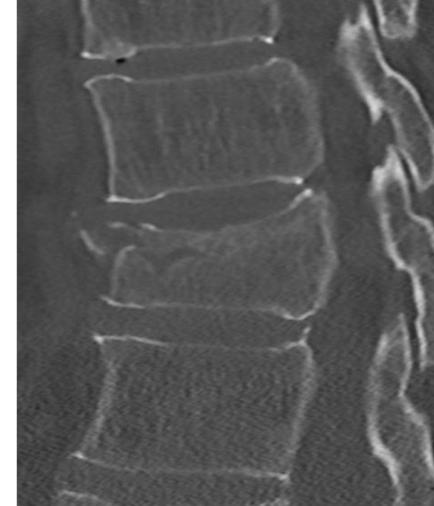

Stabiele of instabiele wervelbreuk

Bij een stabiele wervelbreuk is alleen het wervellichaam gebroken. Als een breuk stabiel is kan het wervellichaam niet verschuiven, waardoor het ruggenmerg niet beschadigd kan raken. Een operatie is dan niet nodig.

Bij een instabiele breuk is dit risico wel aanwezig en daarom is een stabiliserende operatie noodzakelijk. De revalidatie zal grotendeels overeenkomen met de revalidatie na een stabiele breuk zonder operatie.